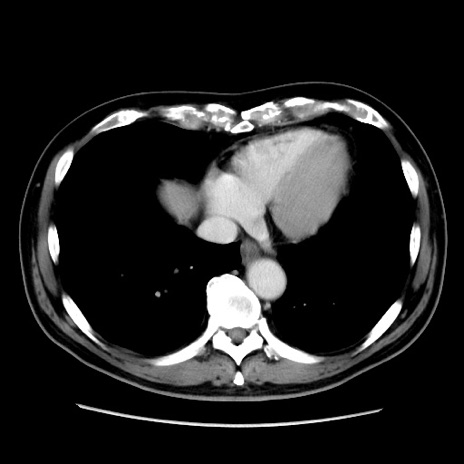

症例16(横断像)

【現病歴】 約1ヶ月前より間欠的に腹痛と嘔吐あり、当院消化器内科を受診したところCTで多発する肝臓のLDAを指摘され、精査中であった。以降は消化器症状は安定していたが、2日前より嘔気と腹痛があり、同日より排便・排ガスが消失した。改善認めず、 本日、救急外来を受診した。